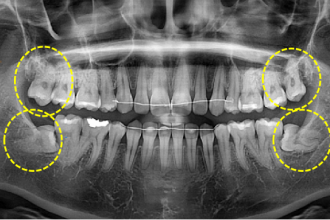

사랑니발치

굿프렌즈 치과 임상 케이스